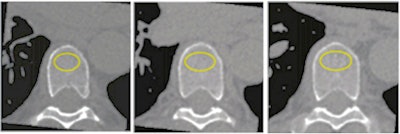

The researchers investigated whether cardiac CT could offer a way to screen for osteoporosis while also assessing heart health: Since these exams visualize the thoracic vertebrae, it's easy to add a bone mineral density test to the procedure, as it doesn't add time or radiation to the exam, the authors noted.

Their study included 1,487 patients who underwent cardiac CT for evaluation of heart disease, and who also had bone mineral density testing of three thoracic vertebrae using quantitative software. The group found that of the total study cohort, 179 (12%) individuals had very low bone mineral density.